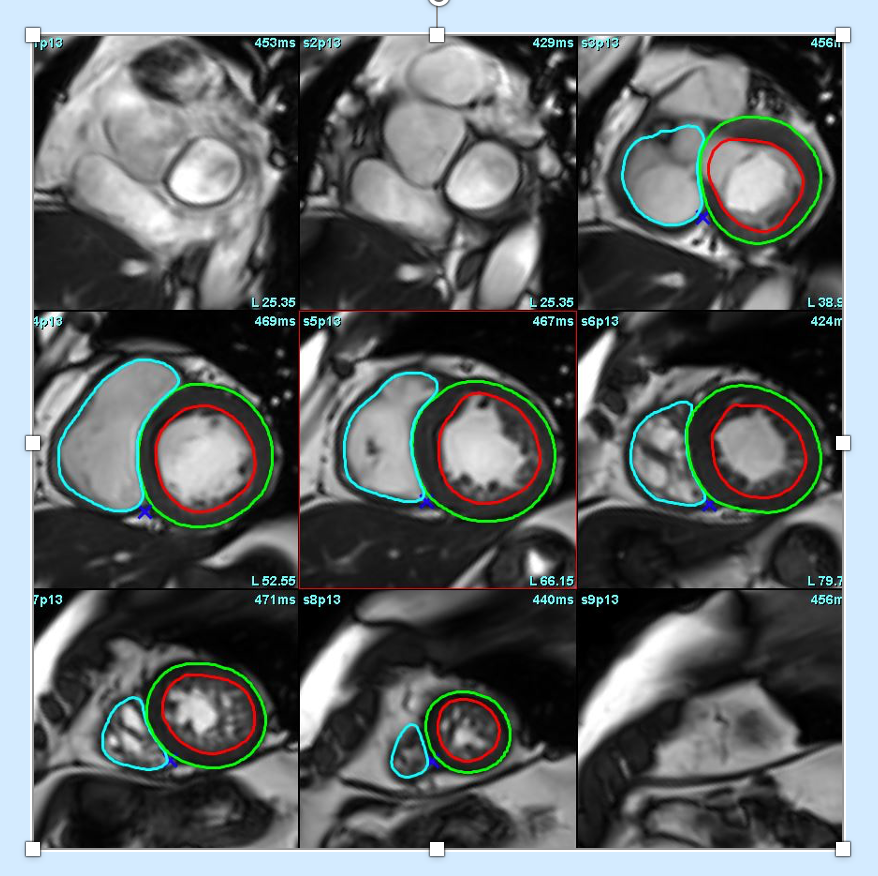

How to do? LV/RV function with CMR